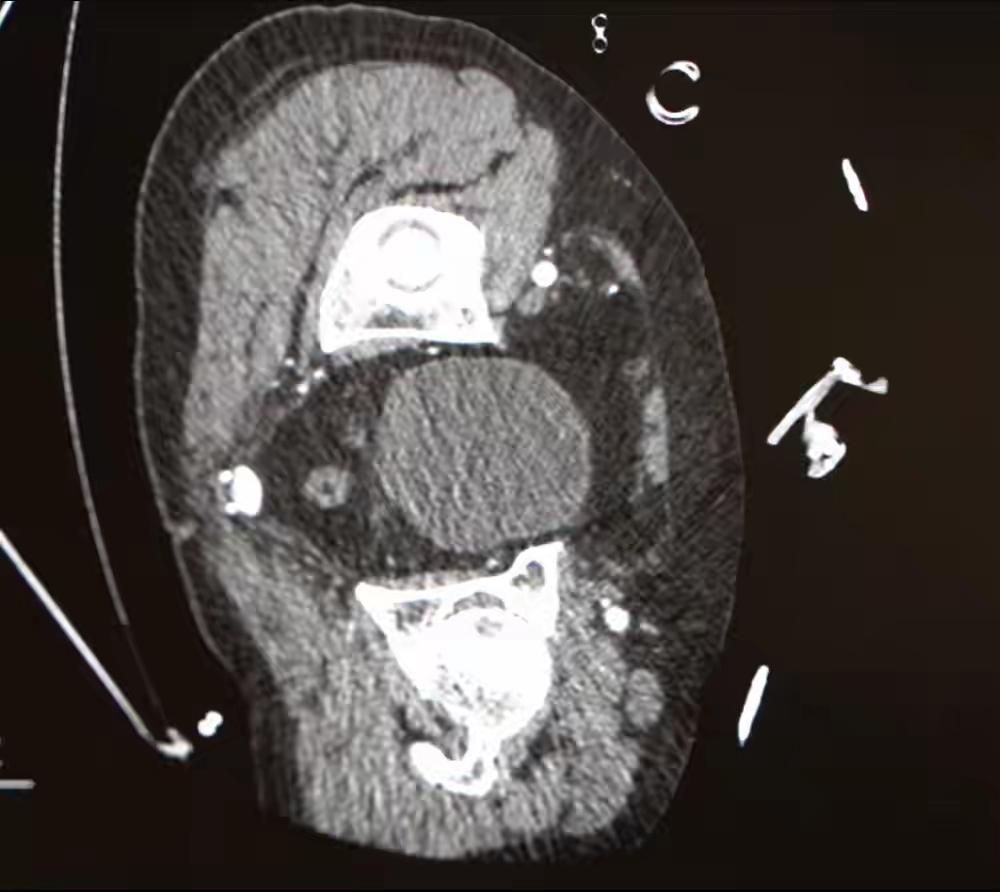

修理师傅弯腰修水管,身体的“主水管”却突然喷血,心脏几乎“空转”!医生提醒:如出现这种症状请立即就医。 近日,陕西西安的修理师傅章先生经历了惊险时刻。当天,章先生正在修理水管,而下一刻他自己的“生命水管”开始疯狂渗血——作为人体血液总管道的胸腹主动脉撕裂,血液正从破口喷涌,左侧胸腔已有1700ml积液,相当于成人全身血量三分之一!他的心脏几乎在“空转”。这是一起极其危急的急症——主动脉撕裂。主动脉是人体中最主要的动脉,负责将血液从心脏输送到全身。一旦主动脉发生撕裂,血液会迅速从血管内喷涌出来,导致大量出血和血容量的快速丧失,危及生命。 关键点分析: 主动脉撕裂的严重性:主动脉撕裂是一种急性、危及生命的疾病,常由高血压、主动脉壁弱点或创伤引起。其症状包括突发剧烈背部或胸部疼痛,疼痛可能呈撕裂样或刀割样。 症状表现: 突然剧烈的胸背痛 出血(如新闻中提到的“喷血”) 休克表现(血压下降、面色苍白、出汗、意识模糊) 心跳加快,甚至心脏“空转”——指心脏因缺血或休克而几乎无法正常泵血。 紧急处理: 立即拨打急救电话 维持呼吸道通畅,避免移动患者 控制出血(如止血带等,需专业操作) 迅速送医,进行手术修复 预防与提醒: 高血压患者应定期监测血压,遵医嘱用药 养成健康生活习惯,避免剧烈运动或创伤 任何突发胸背剧痛都应引起重视,及时就医 总结: 主动脉撕裂是一种极其危险的急症,患者若出现类似剧烈胸背痛、突然出血、意识模糊等症状,应立即就医,争取黄金时间进行救治。公众也应提高认识,重视血压管理和身体信号的变化,以预防此类事件的发生。大动脉爆裂